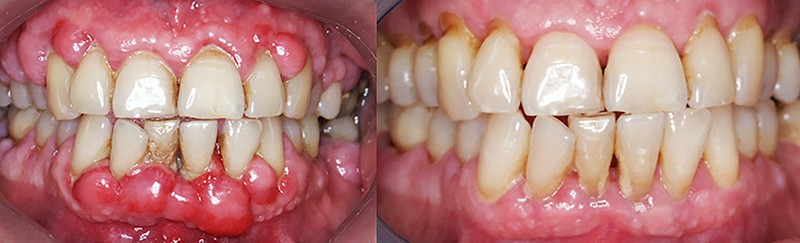

Quand et comment intervenir par voie chirurgicale ? C’est la question à laquelle Filippo Graziani tentera de répondre car, si les techniques de débridement non chirurgical ont permis de repousser les limites des indications chirurgicales, celles-ci sont encore nécessaires (fig. 3a et b). Le choix chirurgical dépend à la fois des objectifs définis initialement avec le patient et des résultats du traitement étiologique. Les séances de chirurgie peuvent être généralisées ou localisées, et faire appel aux différentes techniques d’assainissement, de résection ou d’addition, avec la possibilité de régénération tissulaire par apport de biomatériaux.

L’objectif de cette séance est d’apporter une vue actualisée, claire et précise, nécessaire au dépistage, à la motivation et aux techniques des traitements parodontaux, et de faciliter leur intégration dans l’exercice omnipratique (fig. 4, 5 et 6).